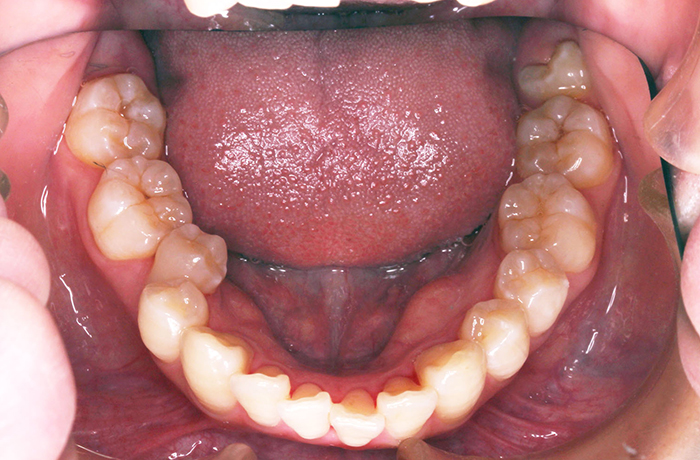

K様

治療前

年齢 27歳

性別 女性

治療名称 マウスピース型カスタムメイド矯正歯科装置(インビザライン)・コンプリヘンシブパッケージ(フルパッケージ)

総額治療費用 770,000円(税込10%) 金額備考 精密検査料・診断料 33,000円(税込10%)

治療期間 1年11か月 通院頻度など 40日ごと

1枚につき10日装着を指示しました。

患者の症状 上顎前歯の前突、八重歯

治療方法 上下左右の第一小臼歯抜歯で、マウスピース型カスタムメイド矯正歯科装置による矯正

治療結果 上顎前歯の前突、八重歯が改善されました。

歯並びをより良くするために追加でアライナーを発注しました。